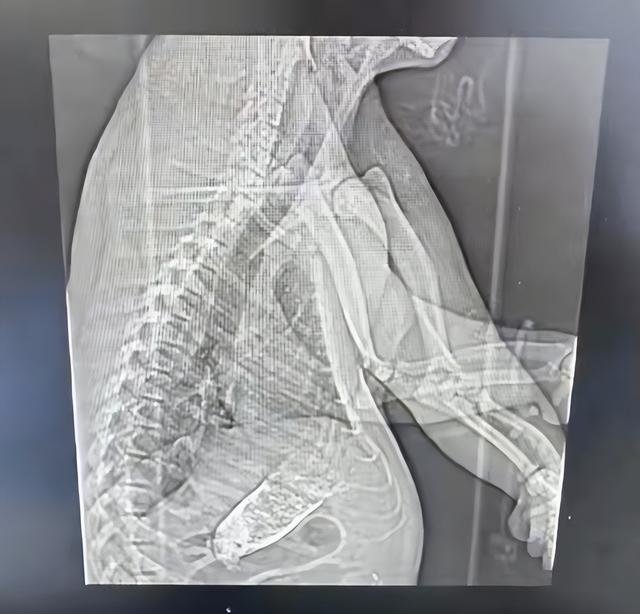

医院拍片患者名为“熊猫”引关注 医护:是真熊猫,得了肠梗阻

根据都市时报报道,近日在上海某医院,一名医护人员看到病人病历名字一栏写着“熊猫”,结果发现是真的国宝大熊猫来看病。该医护人员称,大熊猫可能得的是肠梗阻,希望它快点好起来。

东方网报道,上海野生动物园称,近日大熊猫“七七”近日因肠梗阻紧急送往上海仁济医院南院检查,目前正全力救治。

大熊猫“七七”出生于2018年7月17日,深受上海市民游客喜爱,出生时的体重为165克,目前年满4岁8个月,体重已超过90公斤,平日里活泼好动。